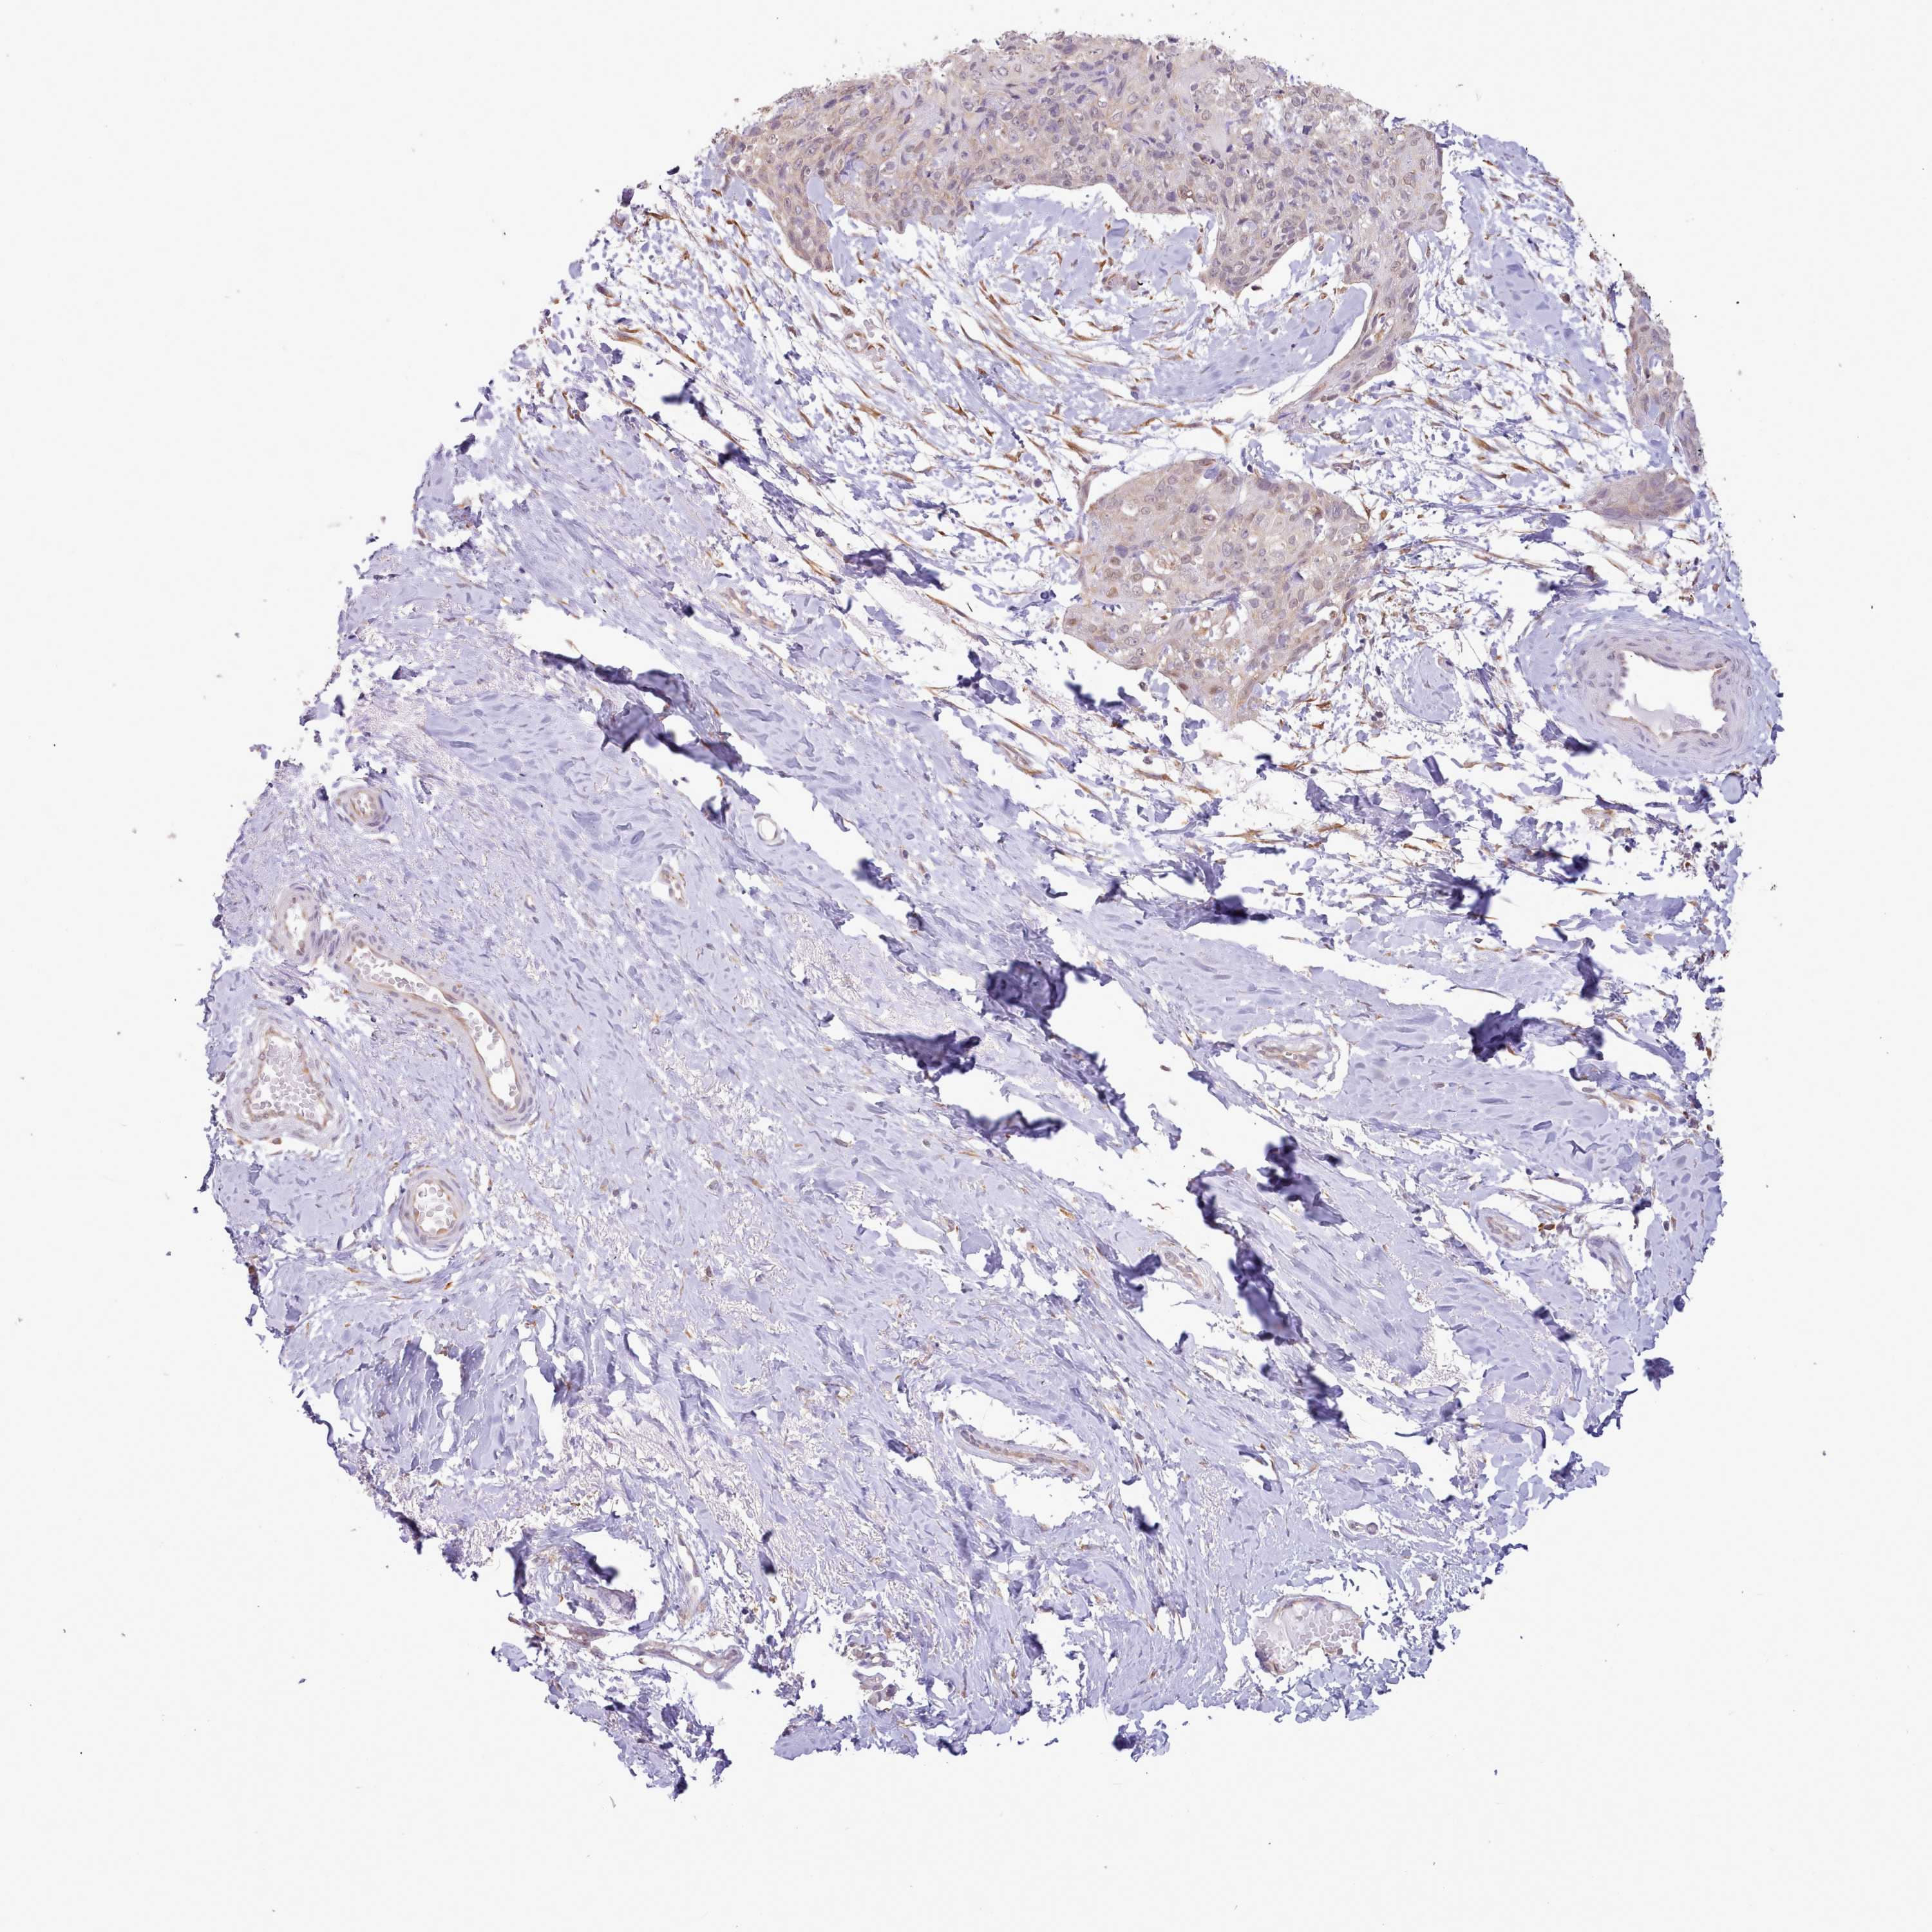

CANCER SKIN CANCER Show tissue menu

Basal cell and squamous cell cancer

SKIN CANCER - Protein expressioni

A mouse-over function shows sample information and annotation data. Click on an image to view it in a full screen mode. Samples can be filtered based on level of antibody staining by selecting one or several of the following categories: high, medium, low and not detected. The assay and annotation is described here.

Each image is clickable and will lead to virtual microscopy that enables deeper exploration of all samples and also displays staining intensity scores, fraction scores and subcellular localization as well as patient and tissue information for each sample.

Antibody HPA049407

Staining

High

Medium

Low

Not detected

Intensity

Strong

Moderate

Weak

Negative

Quantity

>75%

75%-25%

<25%

None

Location

Nuclear

Cytoplasmic/membranous

Cytoplasmic/membranous,nuclear

Basal cell carcinoma

Squamous cell carcinoma, NOS

Squamous cell carcinoma, metastatic, NOS